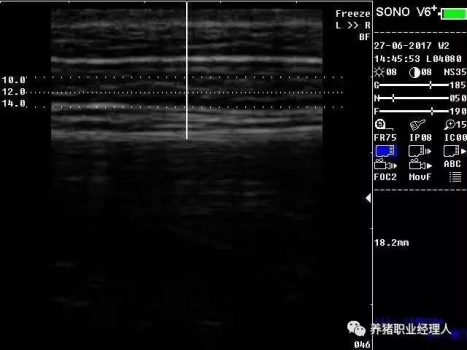

根據(jù)以上表格,活體測(cè)膘與實(shí)體測(cè)膘的相關(guān)分析及活體膘厚與胴體瘦肉率的相關(guān)分析結(jié)果證明,最后肋骨處和腰薦結(jié)合處離背中線5cm處(B5、C5)可作為活體測(cè)膘的最佳部位。 根據(jù)中華人民共和國(guó)農(nóng)業(yè)行業(yè)標(biāo)準(zhǔn)(NY/822-2004)種豬生產(chǎn)性能測(cè)定規(guī)程規(guī)定:生產(chǎn)性能背膘值運(yùn)用A超儀器測(cè)量的需測(cè)定腰薦椎結(jié)合處(P1)、胸腰椎結(jié)合處(P2)距背中線左側(cè)5cm處,兩點(diǎn)背膘厚平均值。生產(chǎn)性能背膘值運(yùn)用B超儀器測(cè)量的需測(cè)定倒數(shù)第三和第四肋骨間距背中線左側(cè)5cm處背膘厚。 2.3 剔剪剪毛 因?yàn)槌暡ㄊ遣荒茉诳諝庵袀鞑サ?,所以在利用儀器測(cè)量之前,先用剔剪剪去測(cè)定部位的豬毛,方便測(cè)量?jī)x器探頭與豬皮膚的無(wú)縫接觸。剪毛面積一般為5cm×5cm左右。此時(shí)若皮膚死皮結(jié)痂較多,便可用溫水擦洗去痂。 2.4涂耦合劑 耦合劑是檢測(cè)儀探頭與豬皮膚之間的中間潤(rùn)滑劑,作為超聲波從儀器發(fā)出到豬體表和從豬體表回到儀器的傳播介質(zhì)。所以耦合劑的作用是排除探頭與豬體表之間的空氣和作為超聲波傳播的介質(zhì)。它是準(zhǔn)確測(cè)定背膘所不能缺少的。 2.5 正確測(cè)量 因?yàn)樨i體表脂肪分為三層。所以不管是用A超還是B超,我們一般都能同時(shí)測(cè)量到三個(gè)數(shù)值,而正確反映豬只體況的是第三個(gè)數(shù)值。如圖所示:

測(cè)量時(shí),盡量讓豬只安靜,避免豬只弓背或塌腰而使測(cè)量數(shù)據(jù)出現(xiàn)偏差。探頭應(yīng)直線平面與豬背正中線縱軸面垂直,不可斜切。同時(shí)探頭應(yīng)與豬背密接且不重壓。 2.6 讀取記錄數(shù)據(jù) 若為A超,讀取儀器亮三個(gè)指示燈時(shí)的數(shù)值,記錄下來(lái)。若為B超,觀察并調(diào)節(jié)屏幕影響,獲得理想影像時(shí)即凍結(jié)影像,測(cè)量背膘厚和眼肌面積,并加以說(shuō)明標(biāo)記。影響打印或保存處理。 3、通過(guò)背膘測(cè)定指導(dǎo)豬生產(chǎn)飼喂管理 以妊娠母豬為例: 表3 妊娠母豬適宜背膘值范圍